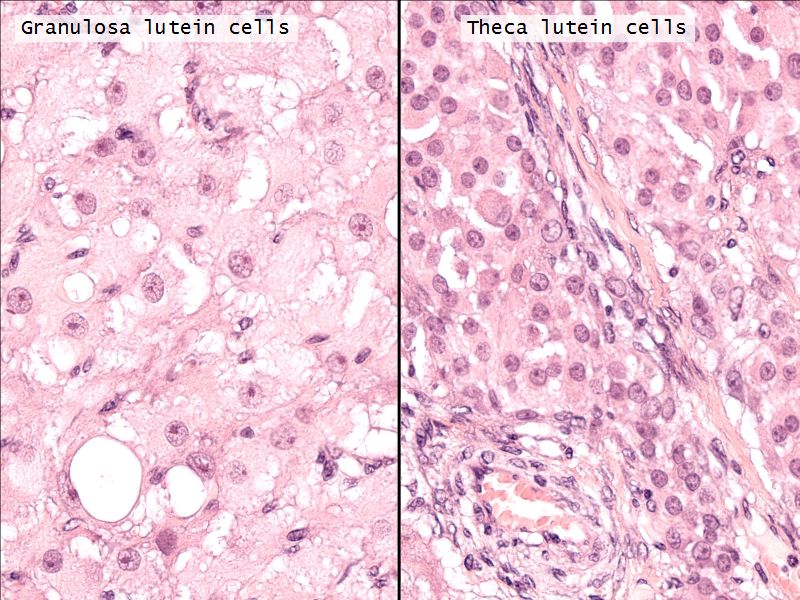

- Two major cell types

- Granulosa lutein cells

- modified granulosa cells

- Theca lutein cells

- modified theca interna cells

- Many capillaries

Granulosa lutein cells

- Modified granulosa cells

- Large - 30µm

- Pale cells

Theca lutein cells

- Modified theca interna cells

- Smaller - 15µm

- Dark stained